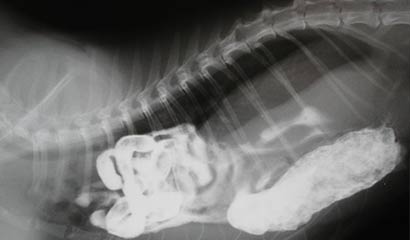

Per la diagnosi certa di ernia diaframmatica si rende imperativo l’ausilio della diagnostica per immagini: radiografie eventualmente anche previa somministrazione del mezzo di contrasto ed esame ecografico. Queste tecniche permetteranno appunto di identificare l’anomala dislocazione in torace di organi che invece devono essere all’interno dell’addome.

L’ernia diaframmatica è una dislocazione congenita o acquisita di organi nella cavità toracica attraverso una lacerazione del diaframma. È definita come “ernia falsa” in quanto i visceri erniati sono sprovvisti del sacco erniario e si trovano dislocati nella cavità pleurica (ernia diaframmatico-pleurica) o nel pericardio (ernia diaframmatico-pericardica).